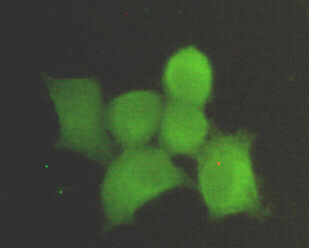

Immunocytochemistry stain of Hela using PPP1CA antibody (1:300).